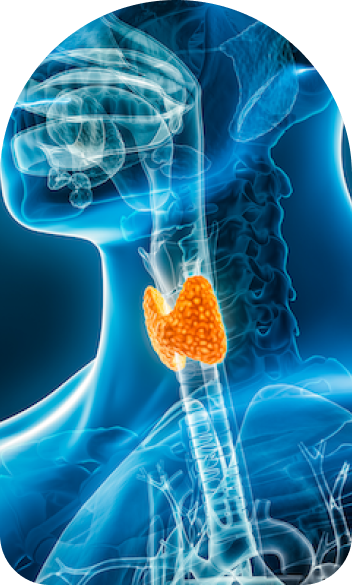

Endoscopic Thyroid Surgery (ETS) is a new surgical method for thyroidectomy, minimizing invasive techniques, while offering the safest and most aesthetic outcome for treatment of thyroid diseases.

There are many types of thyroid disorders ranging from benign nodules to malignancies, which require surgical treatment when medical treatment falls short. Endoscopic Thyroid Surgery has several advantages over standard surgical thyroidectomy. As this technique is minimally invasive, patients experience lesser pain, faster recovery and an aesthetically pleasing result, making it ideal for people who want to minimise visible scarring.

Endoscopic Thyroid Surgery begins with a detailed pre-operative assessment, including imaging and fine-needle aspiration cytology if required. The surgery is typically performed under general anaesthesia. Small incisions are made in inconspicuous areas like the axilla, chest, or behind the ear, through which a high-definition endoscope and specialized instruments are introduced. The surgeon carefully excises the targeted thyroid tissue while monitoring critical structures such as the recurrent laryngeal nerve and parathyroid glands. The removed tissue is sent for histopathological analysis. The procedure concludes with meticulous closure of the incisions, ensuring optimal healing and minimal scarring.